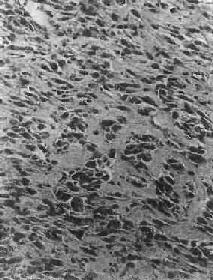

图17-5 骨巨细胞瘤 肿瘤位于肱骨上端,骨皮质破坏,有病理性骨折 镜下,肿瘤主要由单核基质细胞及多核巨细胞等两种细胞组成(图17-6),间质血管丰富。基质细胞为梭形、卵圆形或圆形,细胞境界不清楚,常见胞浆突起。细胞核较大,染色质量中等,可具有一个核仁。多核巨细胞常较均匀地散布在基质细胞之间,是为本瘤的特点。多核巨细胞的直径常为30~60μm,核数一般为15~20个,最多可达100个以上,常聚集在细胞的中央。核的形态与单核基质细胞相似。细胞边界不规则,但分界较清楚,胞浆丰富,略呈嗜碱性,有时还可见含大量脂类的泡沫细胞。本瘤间质血管丰富,有多少不等的胶原纤维。肿瘤本身无成骨现象,但有时见有类骨组织及新生骨小梁,常见于纤维组织的周围,可能是一种反应性新骨形成或病理性骨折后形成的骨痂。

图17-6 骨巨细胞瘤(Ⅰ级) 肿瘤由大量基质细胞和多核巨细胞两种细胞组成 【病理分级】 骨巨细胞瘤在病理组织学上,根据基质细胞和多核巨细胞的数量及异型性的程度分为三级:基质细胞分化好,形态大小一致,偶见核分裂像。多核巨细胞数量多、体积大、细胞核多者为Ⅰ级;基质细胞分化差,异型性明显,细胞密度高,核分裂像多,具有肉瘤样改变。多核巨细胞数量少、体积小、细胞核也少,有明显的异型性者为Ⅲ级;介于两者之间者为Ⅱ级。Ⅰ级基本为良性,具低度侵袭性,刮除术后可复发。多次复发后可变为恶性。Ⅲ级呈恶性肿瘤的表现,易复发和转移至肺。病理分级对判断骨巨细胞瘤的良恶性程度和预后以及治疗方法的选择有一定的参考价值,但并非绝对可靠。 【临床病理联系】 早期症状是局部疼痛及压痛,疼痛性质可为间歇性。位于浅表部位者,可出现局部肿胀或肿块。当肿瘤增大而使表面骨皮质膨胀变薄时,触之有捏乒乓球样感觉。位于脊椎的肿瘤,可引起相应神经压迫症状。 (四)骨肉瘤 骨肉瘤(osteosarcoma)是指肿瘤细胞能直接形成肿瘤性类骨组织或骨组织的恶性肿瘤。骨肉瘤是原发性骨恶性肿瘤中最常见者,约占骨恶性肿瘤的1/3。骨肉瘤的发病率在男性略高,可发生于各级年龄,但最多见于11~20岁,其次为21~30岁,年龄越大,发病率越低。骨肉瘤多发生在骨骼生长发育的旺盛时期,其恶性程度又较高,因此是严重影响劳动生产力并危及生命的重要肿瘤之一,早期诊断及早期治疗具有特别重要意义。 【病因】 骨肉瘤病因不明,其发生与下列因素有关。①骨骼的活跃生长。②放射线:实验证明凡能在骨骼内积存的放射性物质均可诱发骨肉瘤;某些骨疾患如骨巨细胞瘤、动脉瘤性骨囊肿或骨外肿瘤如乳腺瘤、视网膜母细胞瘤等的局部放射线照射治疗,偶尔可引起继发性骨肉瘤。③遗传:视网膜母细胞瘤基因(Rb基因,位于染色体13q14,目前已知它是一种抑癌基因)突变或缺失的遗传性视网膜母细胞瘤患者,发生骨肉瘤的危险性远远高于一般人。近年发现一些骨肉瘤患者也有Rb基因的突变。④病毒:实验证明,动物的骨肉瘤与病毒感染有关,但对人类骨肉瘤尚未有确切的材料说明与病毒的关系。⑤良性骨疾患的恶变:如多发性骨软骨瘤、骨Paget病、骨纤维结构不良等可恶变而发生骨肉瘤,亦称为继发性骨肉瘤。 【病理变化】 骨肉瘤可发生于任何骨,最常见于四肢长骨,半数以上发生于股骨的下端及胫骨或腓骨的上端,其次为肱骨上端。颌骨、脊椎骨、肩胛骨和髂骨等较少见。长骨的骨肉瘤发病年龄较小,发生于扁骨者年龄较大。大多数骨肉瘤发生于骨的内部或中央,在长骨位于干骺端,肿瘤在骨髓腔内及向周围骨皮质浸润形成肿块。因骨骺软骨对骨肉瘤的浸润具有一定的抵抗力,在骨骺板闭合骨化之前(约17~20岁),一般不侵及骨骺端。少数骨肉瘤发生于骨表面,称为皮质旁骨肉瘤,其临床、X线和病理表现均与一般骨肉瘤不同。 肉眼观,长骨肿瘤位于干骺端的骨髓腔中央或为偏心性。一侧或四周的骨皮质被浸润和破坏,其表面的骨外膜常被掀起。在切面上可见肿瘤上、下两端的骨皮质和掀起的骨外膜之间形成三角形隆起,其间堆积由骨外膜产生的新生骨。此三角称为Codman三角,这在X线照片中可以显示出来。在骨外膜被掀起时,自骨外膜通往骨皮质的小血管因受到牵拉而呈垂直于骨皮质分布,在这些垂直的小血管周围,组织的血液供应丰富,故新骨形成增多,这些反应性新生骨小梁呈放射状与骨表面垂直分布(图17-7),在X线上表现为日光放射状阴影,这种现象与上述Codman三角在X线上对骨肉瘤的诊断具有特征性。